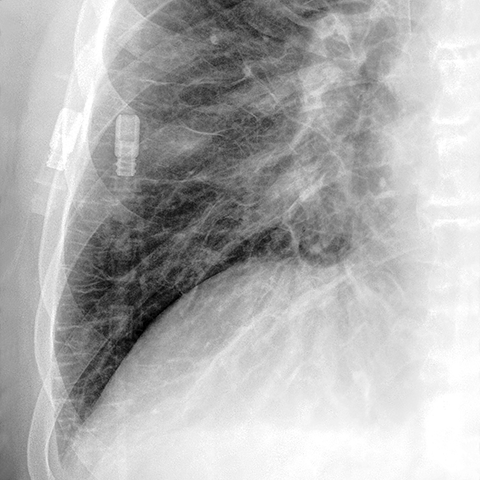

Kerley B Lines